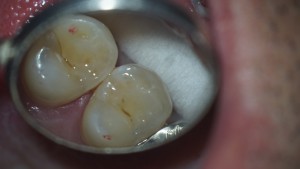

この2本、結構大きい虫歯があります

意外と広がっていてこんな感じに( ゚Д゚)